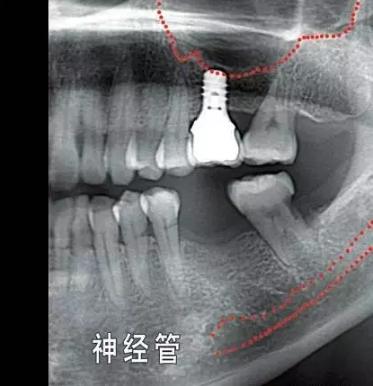

就種植手術(shù)本身而言,您頜面部一些重要結(jié)構(gòu)(例如下頜神經(jīng),上頜竇) 的位置和形態(tài)會(huì)增加手術(shù)風(fēng)險(xiǎn)和操作難度,為避免因手術(shù)損傷這些重要結(jié)構(gòu),醫(yī)院會(huì)要求您手術(shù)前拍攝3D X光片作為參考,以便牙醫(yī)結(jié)合這些材料和您具體分析手術(shù)的風(fēng)險(xiǎn)程度。